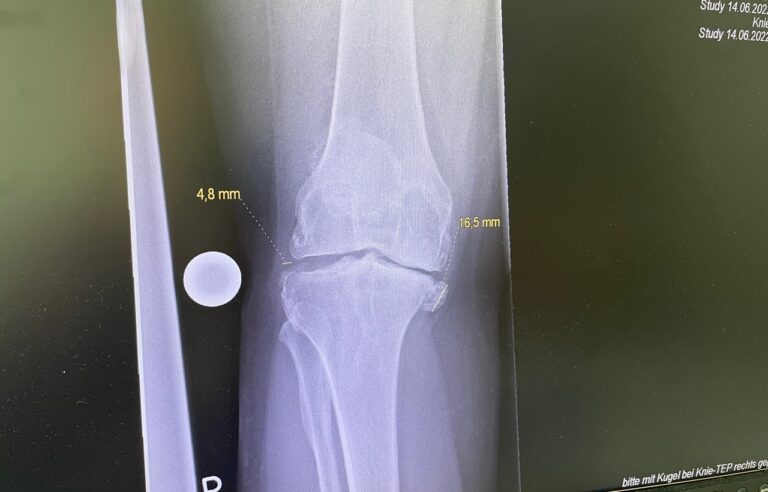

Η ολική αρθροπλαστική γόνατος είναι χειρουργική επέμβαση κατά την οποία αντικαθίσταται η φθαρμένη άρθρωση του γόνατος με τεχνητά εμφυτεύματα.

Στόχος είναι η ανακούφιση από τον πόνο, η βελτίωση της κίνησης και η αποκατάσταση της λειτουργικότητας του γόνατος.

Τεχνική & εξατομίκευση

Η επιλογή της τεχνικής και της πρόθεσης γίνεται εξατομικευμένα, λαμβάνοντας υπόψη:

• την ανατομία του γόνατος

• τον βαθμό φθοράς

Στόχος είναι η σωστή ευθυγράμμιση, η σταθερότητα και το φυσικό εύρος κίνησης.

Σημαντική επισήμανση

Η τελική επιλογή της χειρουργικής τεχνικής γίνεται μετά από αναλυτική κλινική αξιολόγηση και προσεκτικό προεγχειρητικό σχεδιασμό, με στόχο το βέλτιστο και ασφαλέστερο αποτέλεσμα για τον ασθενή. Απαραίτητη προϋπόθεση για την επίτευξη εξαιρετικών αποτελεσμάτων αποτελεί η εξειδίκευση του χειρουργού στη συγκεκριμένη τεχνική, καθώς και η εκτεταμένη εμπειρία με μεγάλο αριθμό επεμβάσεων. Ο έμπειρος ορθοπαιδικός χειρουργός κ. Νικόλαος Καλύβας εφαρμόζει την ολική αρθροπλαστική γόνατο επί σειρά ετών στη Γερμανία, έχοντας χειρουργήσει μεγάλο αριθμό ασθενών. Τα τελευταία χρόνια, από τη θέση του Αναπληρωτή Διευθυντή σε ένα από τα μεγαλύτερα κέντρα αρθροπλαστικής της Γερμανίας, είχε ενεργό ρόλο στην εκπαίδευση ειδικευομένων ορθοπαιδικών στη συγκεκριμένη τεχνική.